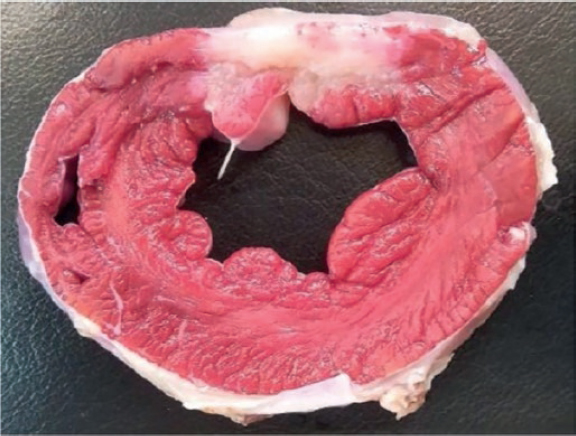

A complete, organized, and systematic necropsy of each animal corpse was conducted to identify and diagnose any possible conditions associated with the procedure. The samples obtained were fixed in formaldehyde at 10% for histopathological study. In the macroscopic study of the heart, its weight was recorded and its cavities, walls, papillary muscles, mitral chordae tendinae, annulus, and valve leaflets analyzed. All the possible anomalies seen in these structures were documented photographically. Afterwards, the leaflets were extracted from their insertion location and up to their free borders including their chordae tendinae and they were fixed in formaldehyde at 10% and included in paraffin for histopathological study. Three µm thick serial sections were stained with the usual hematoxylin and eosin technique; the Van Gieson elastin stain protocol was used to study elastic and collagen fibers; the Masson trichrome stain protocol was used to differentiate muscular from collagen fibers; finally, the alcian-blue PAS staining protocol was used for the detection of mucopolysaccharides. The histopathological changes identified were semi-quantitatively assessed by establishing the different degrees of damage.

After collecting the leaflets to characterize the infarction, another 4 cross-sectional cuts were performed from the vertex of the heart towards its base. They were weighted and stained with triphenyltetrazolium chloride histochemical staining to enhance the viable area (red color) of the necrotic region (white color). For that purposes, the levels established were submerged in a solution of triphenyltetrazolium chloride (Sigma-Aldrich) at 1% in a phosphate buffered saline solution (pH 7.4) for 5 to 10 minutes at 37 °C, and then they were submerged in formaldehyde at 10%. The sections were photographed, and the areas measured using the Image J system. Samples of the infarction region, limit, and non-infarcted region were collected from every level, submerged in paraffin, and stained using the hematoxylin and eosin technique and the Masson trichrome stain protocol to characterize ischemic damage.

Animal #2

The macroscopic evaluation revealed the presence of a transparietal infarction region in the posterior side damaging the medium and basal segments (figure 3) and papillary muscle (figure 4). The spread of this lesion into the different levels is shown on table 2 of the supplementary data.

Figure 3. Animal #2. Presence of transparietal infarction areas from medium (B) to basal level (D). Triphenyltetrazolium chloride stain.

Figure 4. Papillary muscle lesion. Lower part of level C. Triphenyltetrazolium chloride stain.